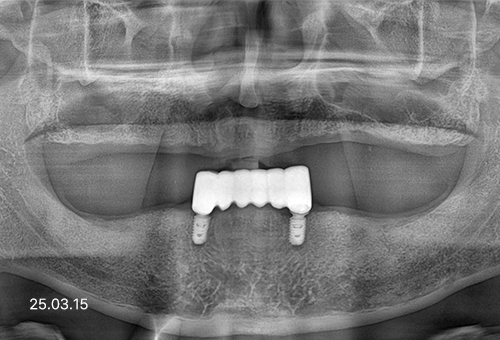

보험 임플란트는 건강보험이 적용되는 치료를 말합니다.

2016년 7월 1일 보건복지부 발표로 도입된 제도로,만 65세 이상 어르신의 기본적인 저작 기능 회복을 돕고자 만들어진 건강보험이 적용되는 치료입니다.

적용대상 : 만 65세 이상

적용개수 : 평생 2개

본인 부담금 : 50% → 30%